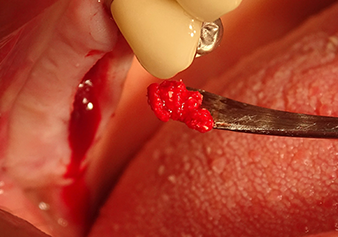

Implant bed preparation and augmentation

Following an intermediate check (Fig. 4) a further preparation step was performed (Fig. 5). Afterwards, the hydraulic Z35P instrument was used to lift the membrane to the desired position (Fig. 6 and 7). This was followed by further piezosurgical preparation of the implant bed, concluded with a rotary bur and shoulder milling cutter up to the implant diameter of 4.8 mm. Before the implant was inserted, the augmentation material (particle size approx. 0.8-1.6 mm) was introduced underneath the Schneiderian membrane (Fig. 8).

Implantation and prosthetic restoration

To move the augmentation material in the direction of the maxillary sinus atraumatically, the implant was inserted very slowly by hand (Fig. 9). In the process, the membrane was pushed in the cranial direction once again. After two months, the surgical site healed without irritation. Six months later, the x-ray check showed a significant increase in opacity as an indication of ossification (Fig. 10). The prosthetic restoration was carried out with a metal-ceramic crown.